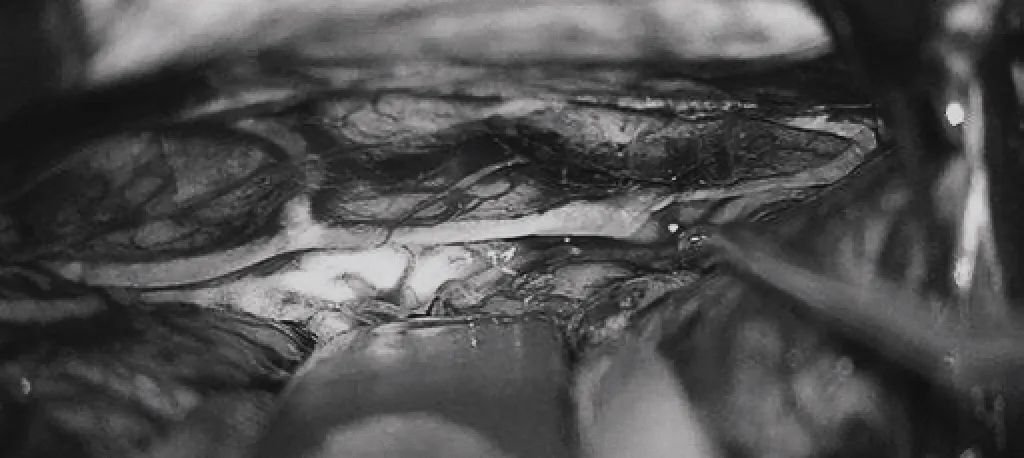

▼(c)双额开颅,打开纵裂(鼻朝右,中线水平位,重力牵拉右侧半球),显露胼胝体、CmaA和PcaA。(d)切开胼胝体2.5cm,显露透明隔内的AVM,大致显露ACA。